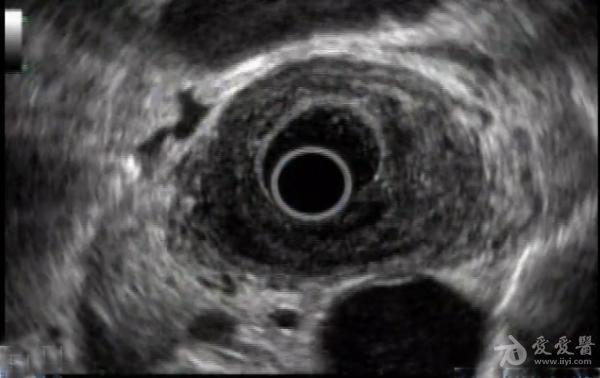

【一般情况】 患者,男性,65岁, 【既往史】 吞咽困难1年。 【辅助检查】 上消化道内镜检查显示可见白色疣状渗出性病变累及中下段食道。整个食管粘膜质脆,可见食管下段管腔变窄,但内镜可以通过。从这种病变的活检显示中度至重度异型性角化过度和角化不全灶。 【诊断】 疑为疣状癌。